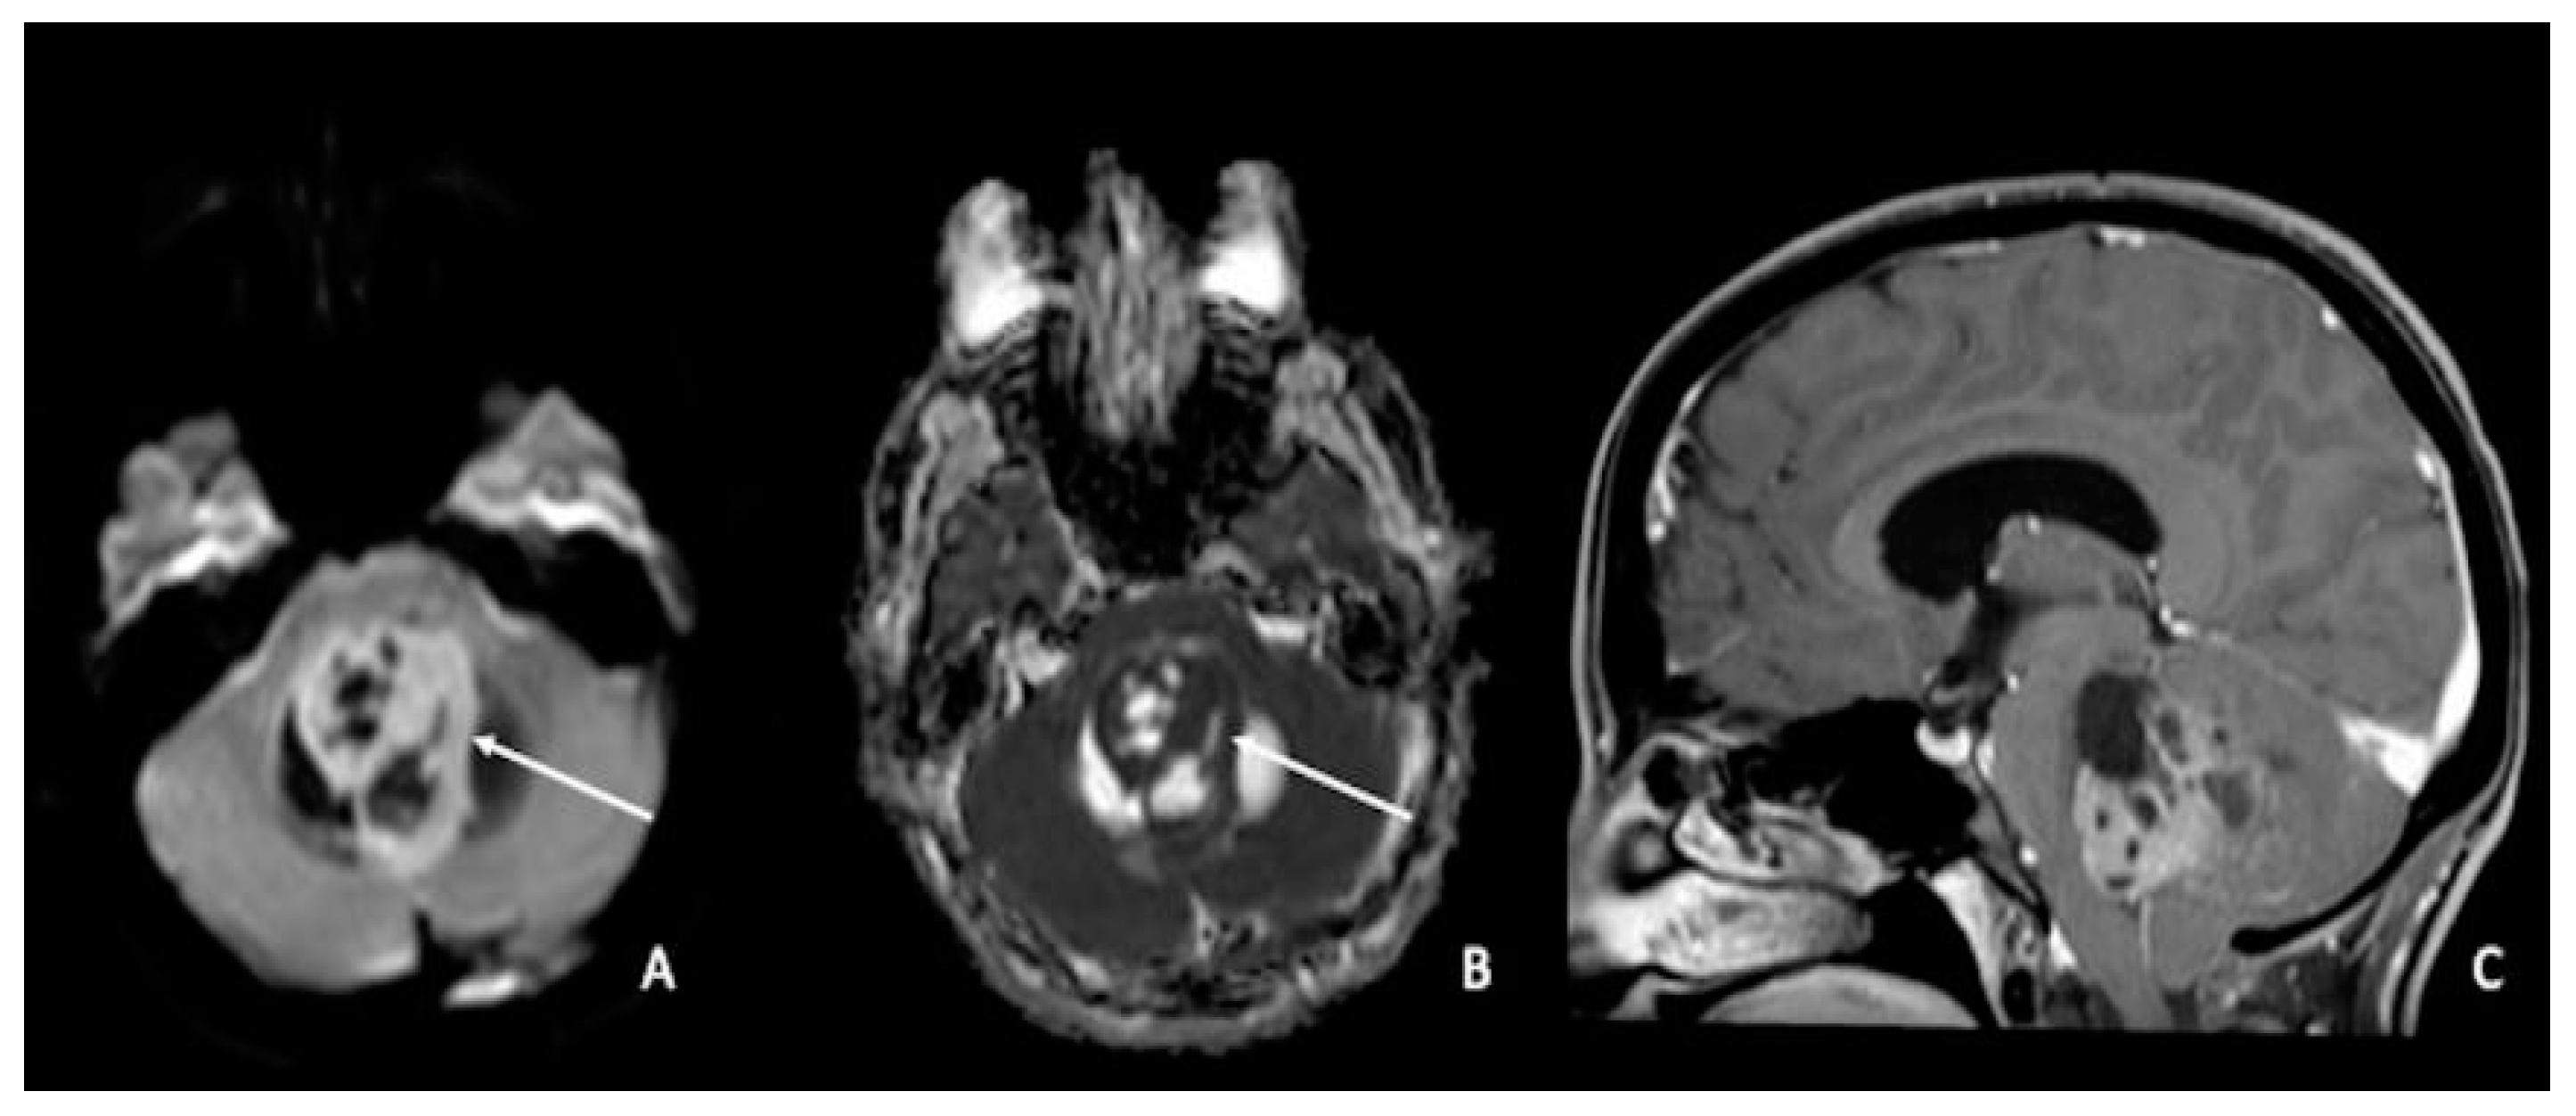

5. Medulloblastomas

- Yamashita, Y.; Kumabe, T.; Higano, S.; Watanabe, M.; Tominaga, T. Minimum apparent diffusion coefficient is significantly correlated with cellularity in medulloblastomas. Neurol. Res. 2009, 31, 940–946. [Google Scholar] [CrossRef]

- Rasalkar, D.D.; Chu, W.C.; Paunipagar, B.K.; Cheng, F.W.; Li, C.K. Paediatric intra-axial posterior fossa tumours: Pictorial review. Postgrad. Med. J. 2013, 89, 39–46. [Google Scholar] [CrossRef]

- Fruehwald-Pallamar, J.; Puchner, S.B.; Rossi, A.; Garre, M.L.; Cama, A.; Koelblinger, C.; Osborn, A.G.; Thurnher, M.M. Magnetic resonance imaging spectrum of medulloblastoma. Neuroradiology 2011, 53, 387–396. [Google Scholar] [CrossRef]

- Plaza, M.J.; Borja, M.J.; Altman, N.; Saigal, G. Conventional and advanced MRI features of pediatric intracranial tumors: Posterior fossa and suprasellar tumors. AJR Am. J. Roentgenol. 2013, 200, 1115–1124. [Google Scholar] [CrossRef]

- Dangouloff-Ros, V.; Varlet, P.; Levy, R.; Beccaria, K.; Puget, S.; Dufour, C.; Boddaert, N. Imaging features of medulloblastoma: Conventional imaging, diffusion-weighted imaging, perfusion-weighted imaging, and spectroscopy: From general features to subtypes and characteristics. Neurochirurgie 2021, 67, 6–13. [Google Scholar] [CrossRef]